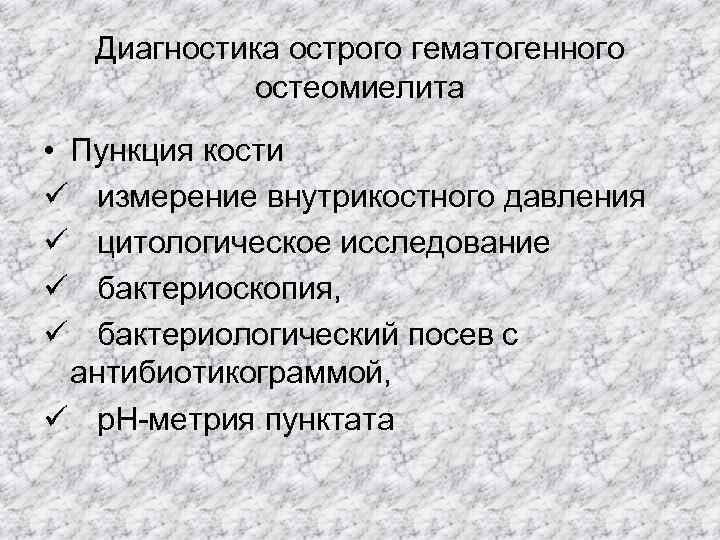

Диагностика острого гематогенного остеомиелита • Пункция кости ü измерение внутрикостного давления ü цитологическое исследование ü бактериоскопия, ü бактериологический посев с антибиотикограммой, ü р. Н-метрия пунктата

Диагностика острого гематогенного остеомиелита • Пункция кости ü измерение внутрикостного давления ü цитологическое исследование ü бактериоскопия, ü бактериологический посев с антибиотикограммой, ü р. Н-метрия пунктата